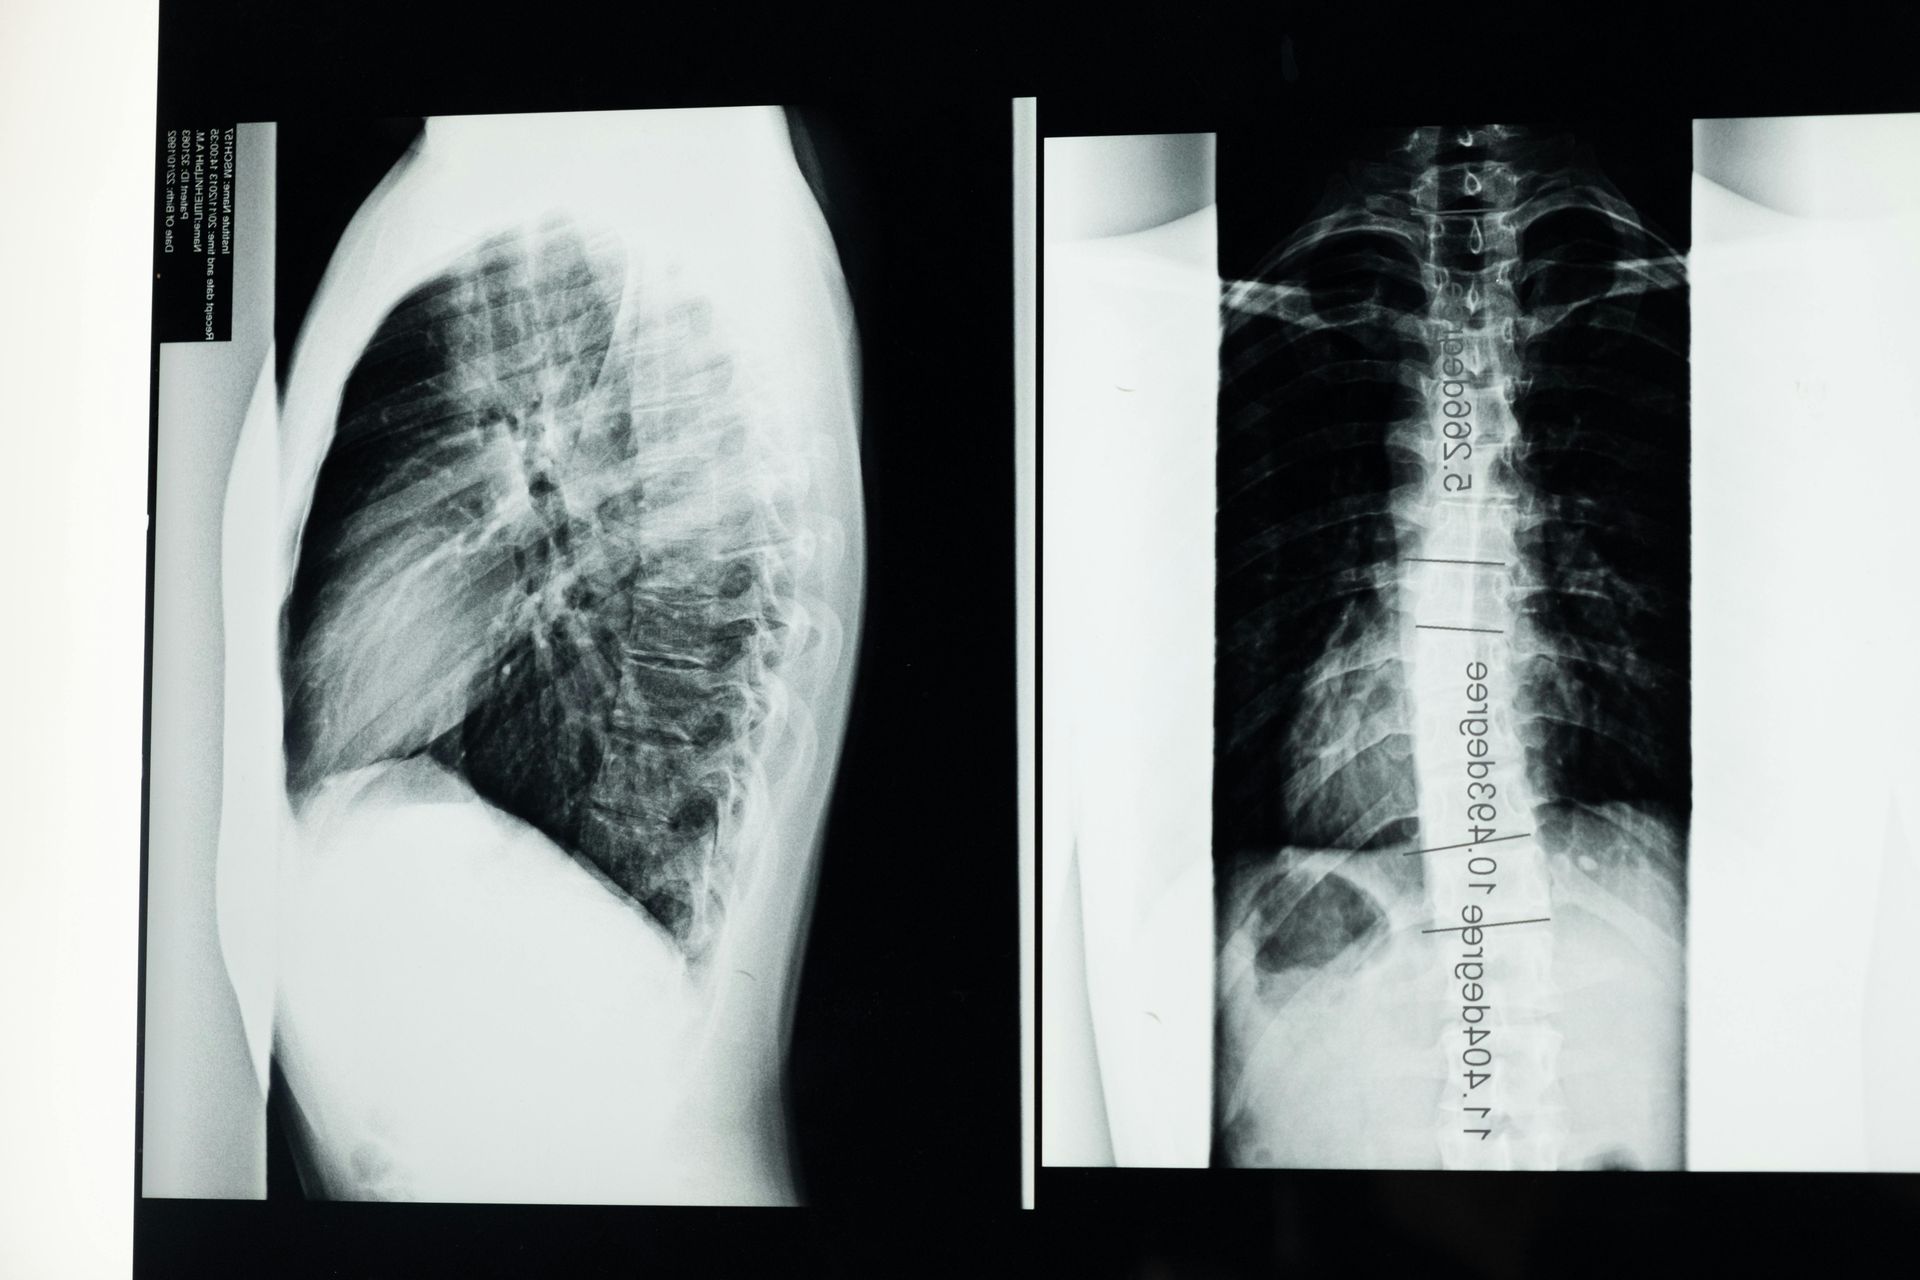

Medical Evidence Is Critical

The strength of a back fusion disability case often depends on the medical evidence.

Important records may include:

- Surgical reports

- MRI or CT scan results

- Physical therapy records

- Pain management treatment notes

- Neurological examinations

- Medical source statements from treating doctors

These records help demonstrate the severity of your condition and how it affects your ability to work.